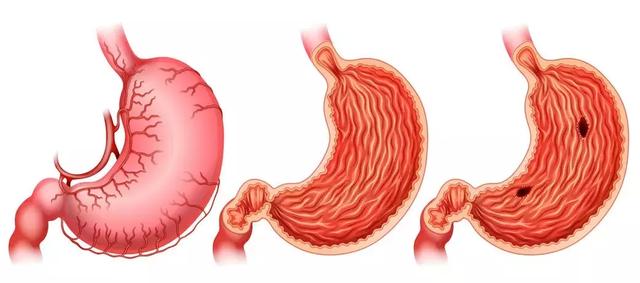

胃病很常見,主要臨床表現為胃痛,大多由於人們的情緒因素、飲食不健康、作息不規律,沒有註意保養胃,導致越來越多的人患上了胃病,今天我們聊聊胃痛吃什麼食物好。

胃痛又稱胃脘痛。如果將腹部劃分為四個區域來看,左側偏中上的部分這一區域的疼痛,最有可能是胃痛。廣義來講,平肚臍以上至肋弓劍突下都屬於胃的區域。

導致胃痛的原因有很多,如胃酸、膽汁返流引起的、患有胃潰瘍、十二指腸潰瘍潰瘍、胃痙攣等,大多與進食有很密切的關係。